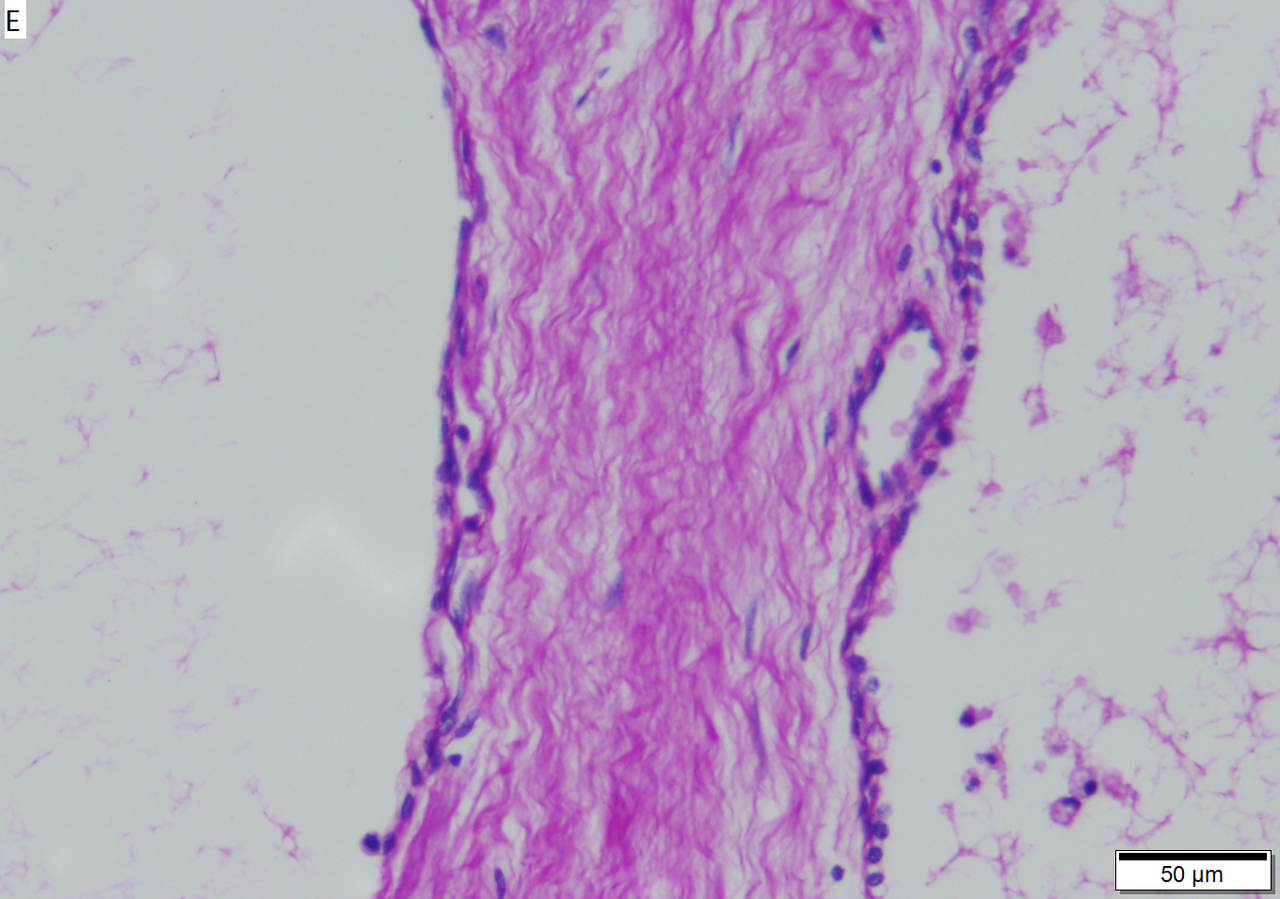

Microcystic serous cystadenoma of pancreas in a 62 year old woman. A. The tumor showed a central scar with multiple minute cysts; slight pressure yielded clear fluid. B. The mass comprises microcysts numberless. C. Cysts bear single cell linings with bland, amitotic nuclei. D. PAS without diastase shows positive cytoplasmic material. E. PAS with diastase shows the cytoplasmic material has been digested away. F. Keratin shows positive staining lining cells.